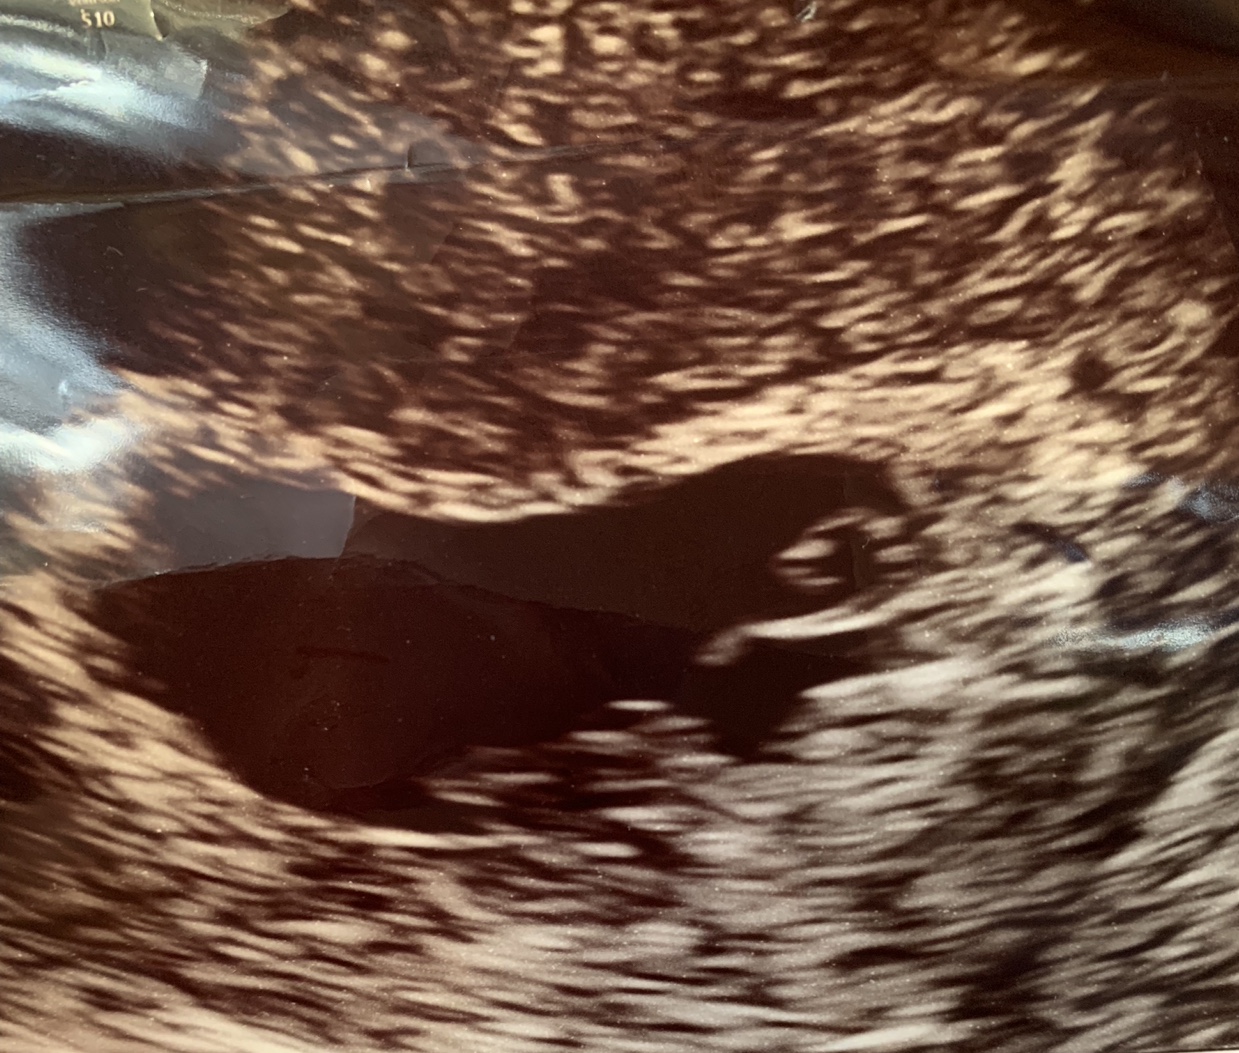

One pic is Ramzi at 7w3d; the other is nub (i think?!) at 12w3d....

The nub isn't clear in the 12 week pic plus it's a bit early anyway. Sorry!